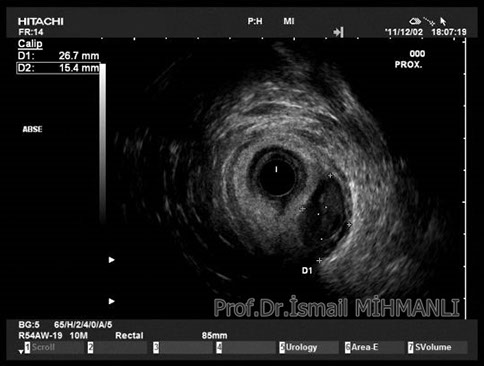

PERİANAL FİSTÜLLER Perianal fistül ve abselerin intersfinkterik anal bez iltihabından kaynaklandığı düşünülmektedir. Crohn hastalarında perianal enflamatuvar hastalık sıktır. İntersfinkterik mesafedeki enfeksiyon yukarıda rektuma, aşağıda cilde, yanlarda dış sfinkteri geçerek iskiyoanal mesafeye uzanabilir. Primer fistülün sfinkterler ile ilişkisini ve abse veya sekonder dal varlığını ameliyat öncesi bilmek, tedavi planı açısından önemlidir. İskiyoanal ve iskiyorektal mesafe tutulmamışsa hastalık daha kolay tedavi edilir. Bu mesafelerde abse veya sekonder bir dal varsa fistül komplekstir ve tedavisi kompleks olmayan fistüle göre değişik olabilir. Bundan dolayı, primer fistül traktı anatomik yerleşimine göre geleneksel olarak sınıflandırılır. Bu sınıflama dörde ayrılır: 1- İntersfinkterik (iç ve dış sfinkter arasında), 2- Transsfinkterik (dış sfinkteri geçerek iskiyoanal veya iskiyorektal mesafeye ulaşmış), 3- Suprasfinkterik (intersfinkterik plandan yukarı doğru uzanan traktüs puborektal kasın Genel Gaz ve Dışkı Kaçırma (Anal İnkontinans) Perianal Fistüller Rektal Tümörler Anal Tümörler Kabızlık Yazılarımız üstündeki bir seviyeden yana kıvrılarak tekrar aşağıya iskiyoanal mesafeye uzanmış), 4- Ekstrasfinkterik (sfinkterlerin dış tarafında rektumdan direkt olarak perianal cilde uzanan traktüs). Endoanal ultrason ile hem primer fistül, hem de varsa sekonder dal ve abse doğru bir şekilde tanınır. Endoanal ultrason ile fistülün anal kanala açılan kısmını (iç uç) görmek kolaydır. Bu hastalarda sfinkter defektlerine de rastlanmaktadır. Sfinkter defekti endoanal ultrason ile kolaylıkla tespit edilir. (bkz. anal inkontinans) Perianal fistül şikayeti olan hastaların az kısmında endoanal ultrason ile bir şey görülemez ise endoanal ultrason probuna ek olarak lineer prob ile anal kanal çevresine bakmak yararlıdır. Çünkü anal kanal bileşenlerinin uzağındaki bir enflamasyon ancak bu problar ile tanınabilir.